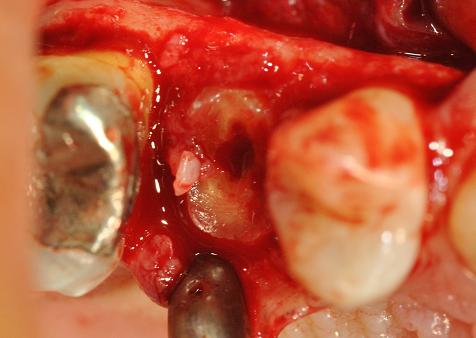

misurazione dellalveolo post-estrattivo

con inserto IM1 si esegue un imprinting della preparazione implantare sul versante palatino dell'alveolo

preparazione differenziale del sito implantare con OT4 dopo espansione con sentineri da 2.5 mm e IM2

inserzione impianto sec da 4.3mm e 12mm IMPLADENT (FORMIA, LT)

ESPANSORE A VITE DI SENTINERI

IMPINTO IN SITU, SI DECIDE DI COLMARE IL GAP CON BIO-OSS